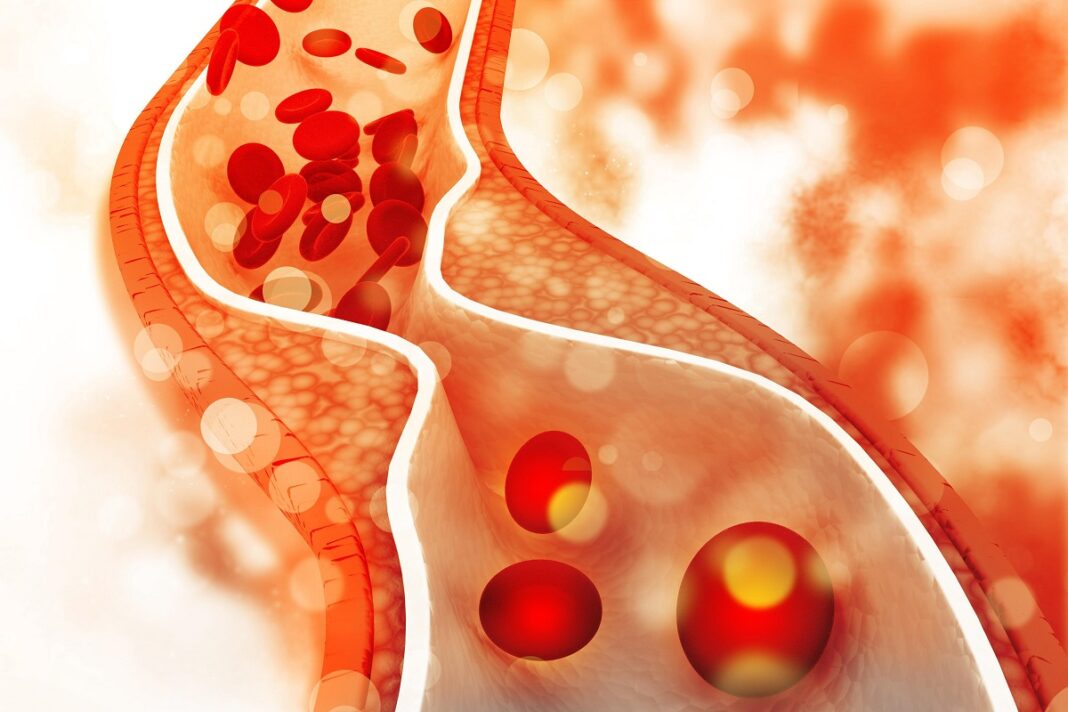

Το πρωινό είναι το πιο σημαντικό γεύμα της ημέρας… κι ας το σνομπάρουμε, ιδίως εδώ στην Ελλάδα. Με το κατάλληλο πρωινό μπορούμε να καταπολεμήσουμε ακόμα και την χοληστερίνη αυξάνει τον κίνδυνο για έμφραγμα και εγκεφαλικό.

Έρευνα του 2020 σε ενήλικες διαπίστωσε ότι τι να παραλείπεται το πρωινό γεύμα μπορεί να σχετίζεται με αύξηση της χοληστερόλης λιποπρωτεϊνών χαμηλής πυκνότητας (LDL).

Μια ανασκόπηση επιμέρους ερευνών εξέτασε τα αποτελέσματα της παράλειψης πρωινού σε παιδιά και εφήβους. Διαπίστωσε ότι αυτή η πρακτική μπορεί να σχετίζεται με παράγοντες καρδιομεταβολικού κινδύνου, συμπεριλαμβανομένης της υψηλότερης LDL χοληστερόλης. Ωστόσο, απαιτείται ακόμη πρόσθετη έρευνα για να υποστηριχθεί αυτό το συμπέρασμα.

Οι τροφές που επιλέγετε για πρωινό μπορούν να συμβάλουν σημαντικά στην μείωση της “κακής” χοληστερόλης (LDL) και στην αύξηση της “καλής” χοληστερόλης (HDL).